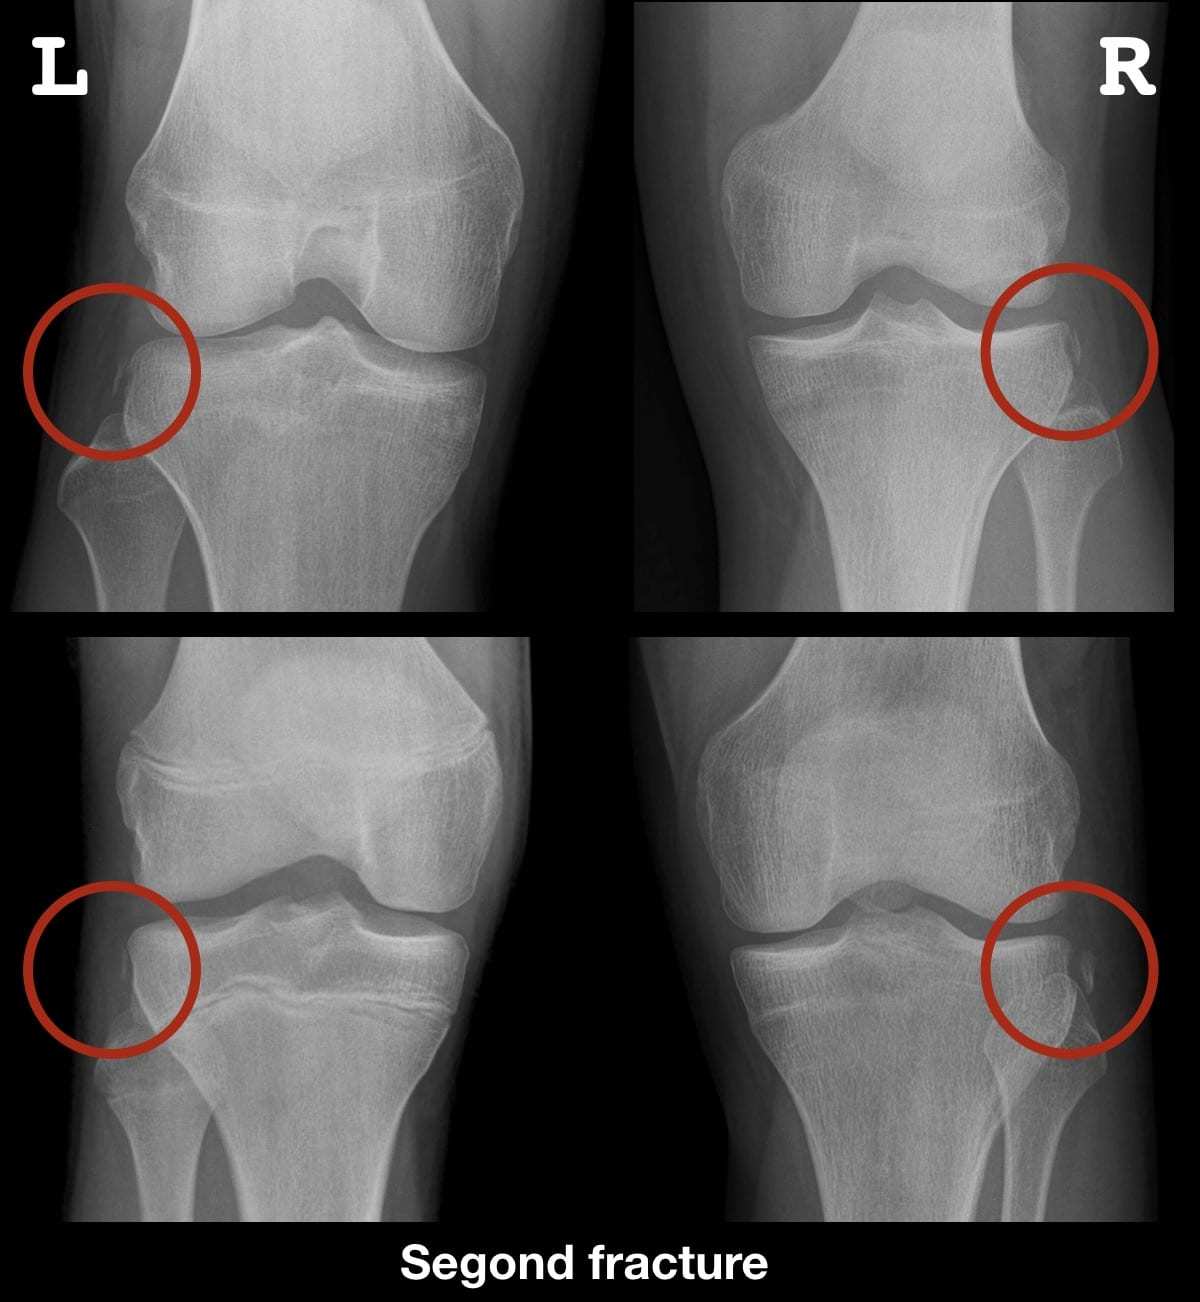

RX:

Fratura de segond - Avulsão do planalto lateral = patognomônico para lesão do LCA